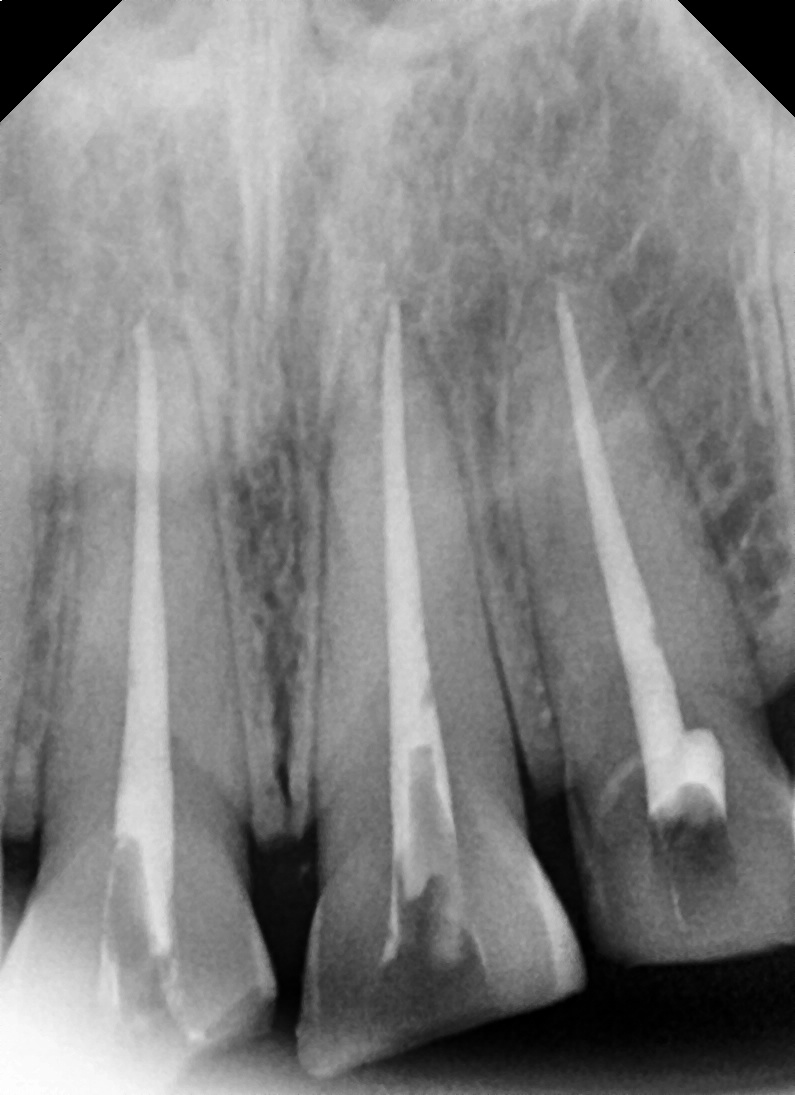

치료과정

치료기간: 2025년 7월 18일 ~ 2025년 8월 8일 (약 3주)

① 신경치료

– 치아 내부에 염증과 손상된 신경을 제거하고,

치근관 치료를 통해 감염을 막았습니다.

② 치아 형태 다듬기

– 크라운이 잘 맞도록 치아를 다듬은 후

임시 보철물을 장착했습니다.

③ 최종 크라운 제작

– 병원 내 기공소에서 지르코니아

크라운을 맞춤 제작했습니다.